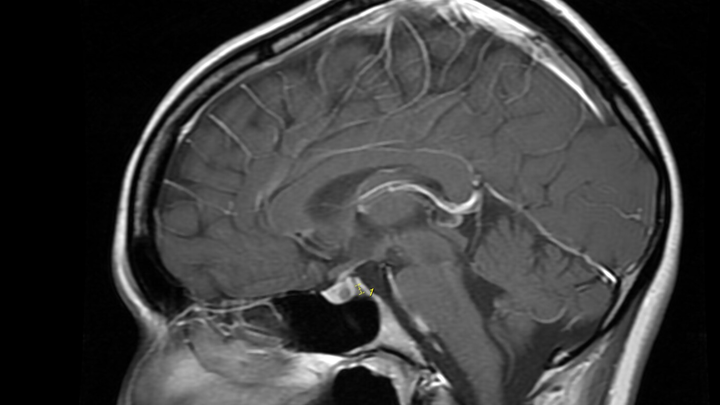

My name is Bri, and I am 22 years old. I've been experiencing migraines, balance changes, and vision changes. I was referred to a neurologist, and they ordered a brain MRI, where they found a tumor in my pituitary gland that is causing these problems. This tumor is also messing with my hormones and causing low cortisol, which was tested by my neurosurgeon. My surgery will be performed on April 7, and I was told I need to be on medical leave from my job for at least a month. It will be hard for me to stay out of work since I have a few bills that I need to take care of, and I do not want to stress about them while I am recovering. I want to have a stress-free and good recovery. My family will be with me while I recover. Thank you for reading.